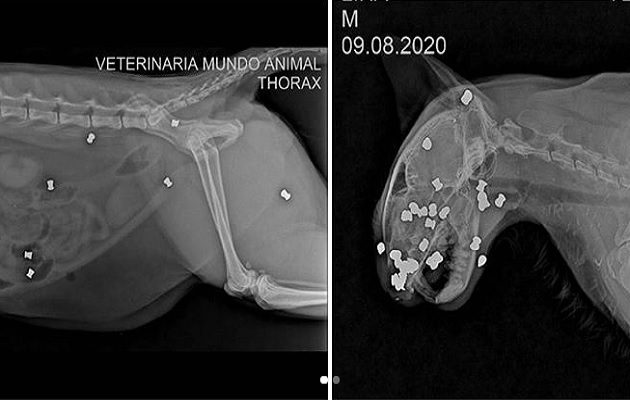

En primera instancia pensó que lo habían atropellado, pero la sorpresa negativa llegó cuando le practicaron las radiografías.

"Eran balazos de balines alrededor de toda su cara, nariz y cráneo y también otras partes del cuerpo", explicó.